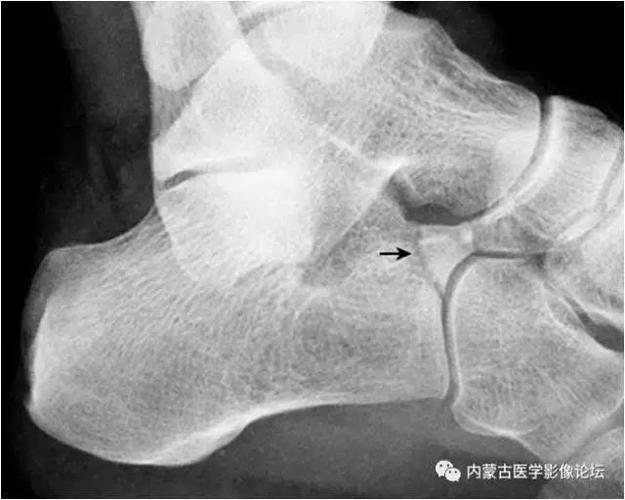

跟痛症,跟骨刺,足底跖筋膜炎(跟骨x线片)

足x线的正常表现及常见病变